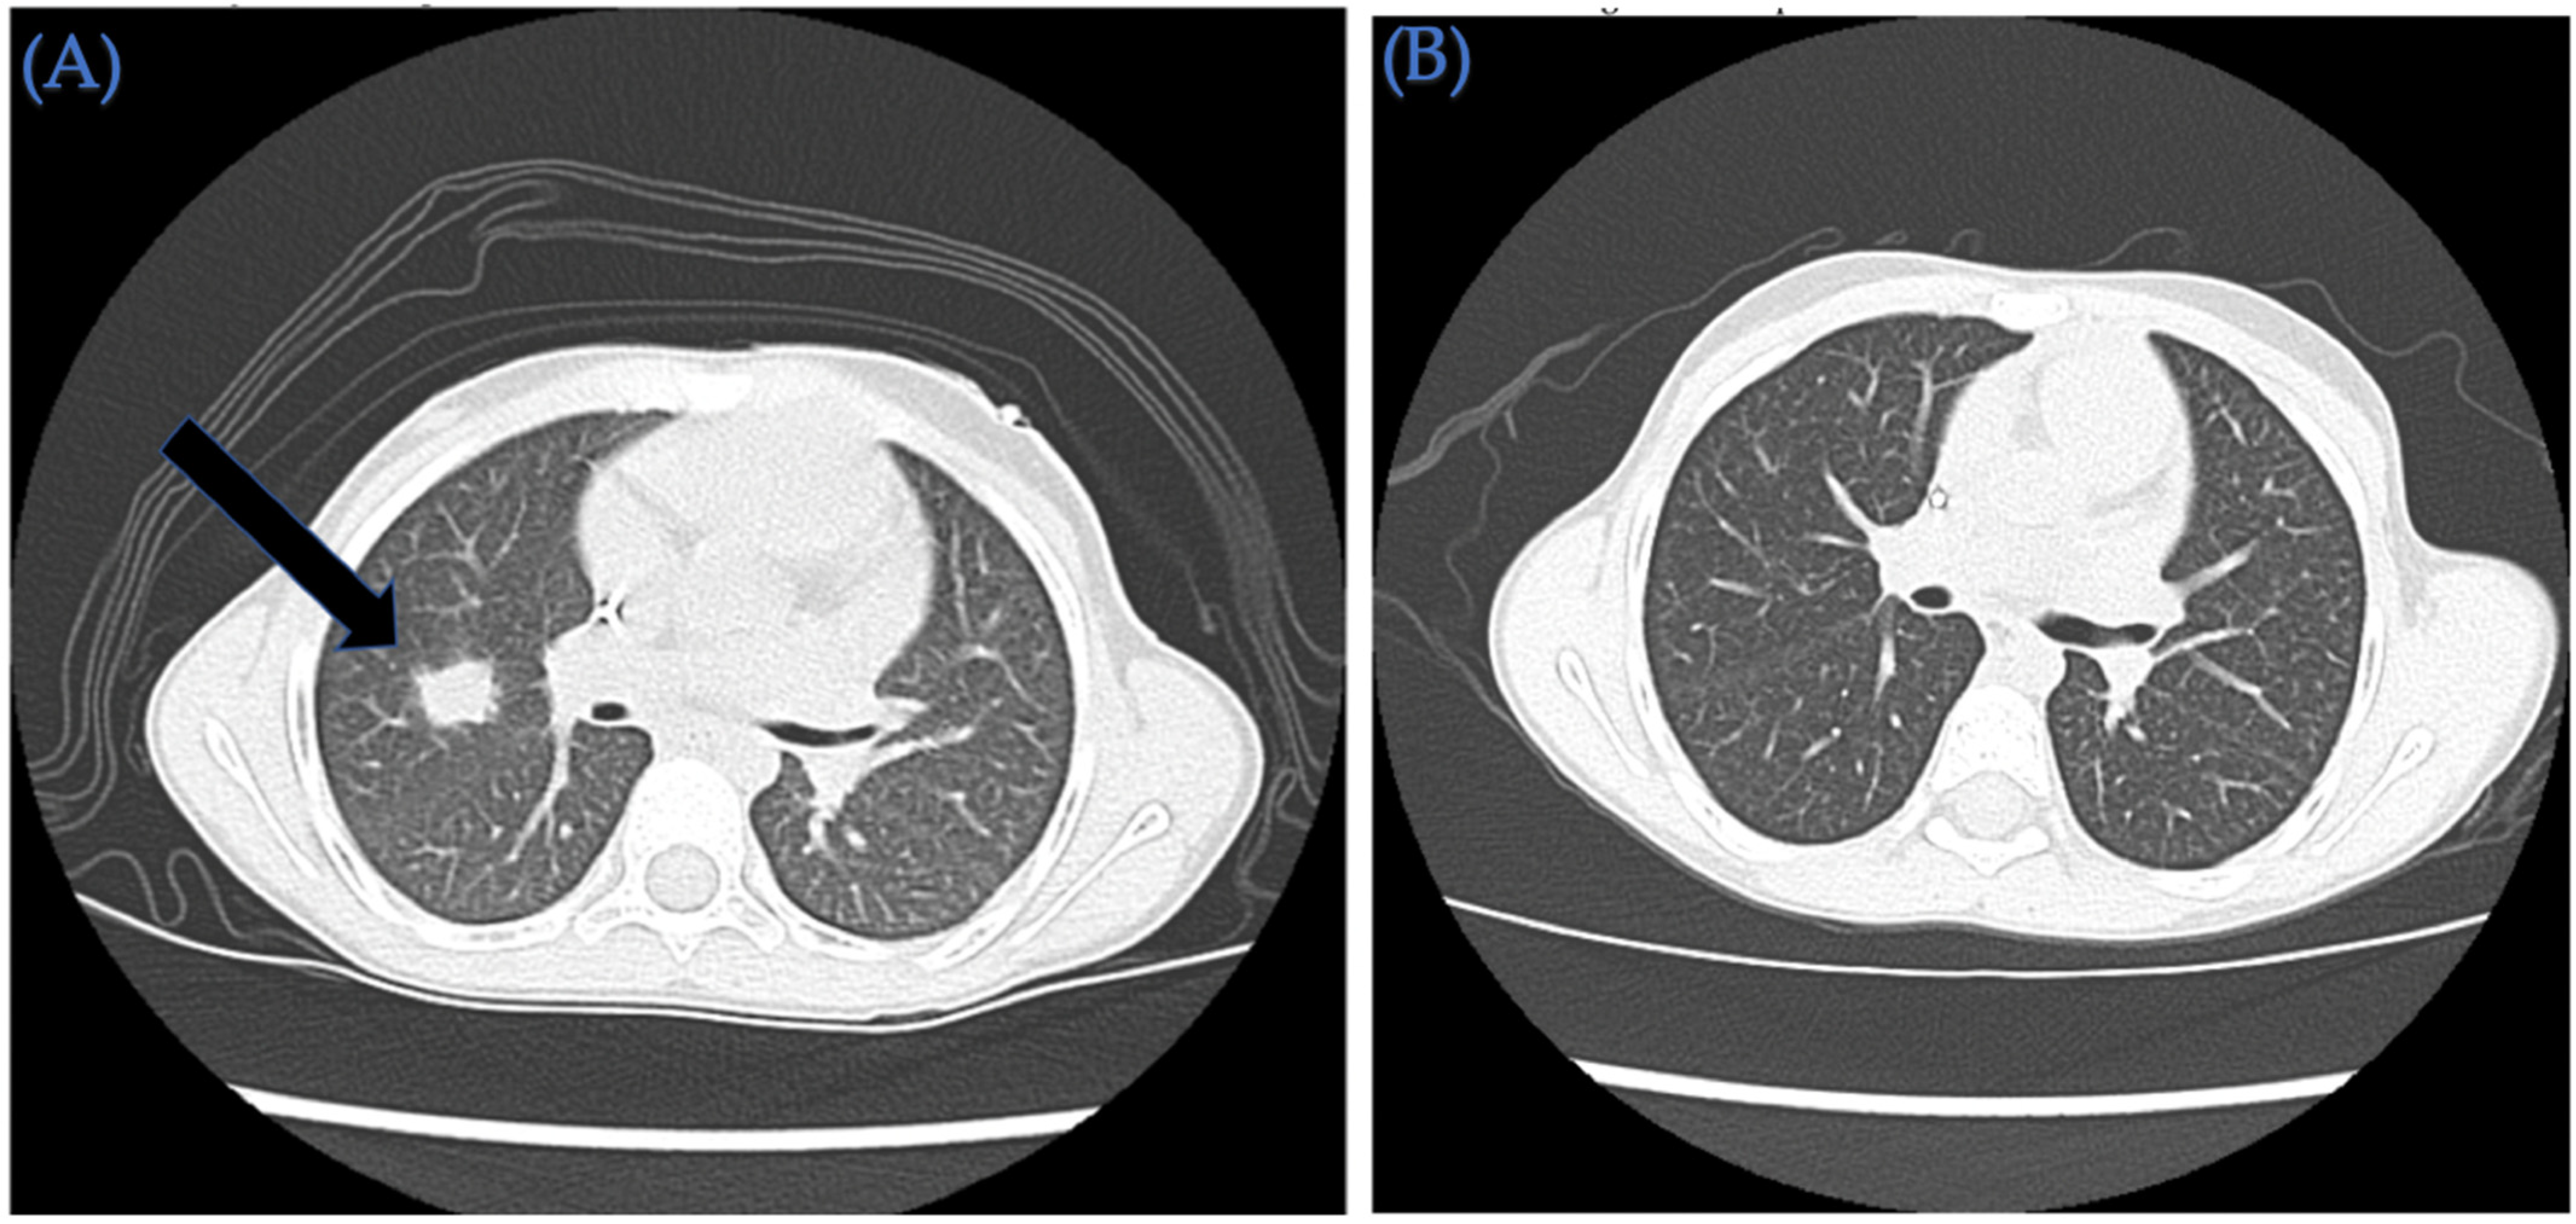

| 2 | 11/M | Relapsed refractory acute myeloid leukemia with reciprocal translocation 11q23 and 19p13.1, FLT3-ITD with allelic ratio of 0.91, NPM1 negative, FLT3-TKD negative | CR2 | Pulmonary toxoplasmosis | BM/MSD | 14/14 | TNC: 1.99 × 108/kg CD34+: 2.3 × 106/kg | M/F | A+/A+ | +/+ | IV PTCy 50 mg/kg on days +3 and +4 followed by MMF and tacrolimus starting day +5 | +17/+31 | +194 |

| 3 | 6/F | Very high risk acute myeloid leukemia with t(6;9) (p23;q34) and DEK/NUP214 fusion and FLT3-ITD positive (allelic ratio 0.75) | CR1 | Invasive pulmonary aspergillus infection requiring triple anti-fungal therapy (Voriconazole, liposomal amphotericin and caspofungin) SARS-CoV-2 infection treated with remdesivir | PBSC/MUD | 10/10 | TNC: 14.6 × 108/kg CD34+: 7.6 × 106/kg | F/M | O+/O+ | +/+ | IV PTCy 50 mg/kg on day +3 and +4 followed by MMF and tacrolimus starting day +5 | +16/+31 | +183 |